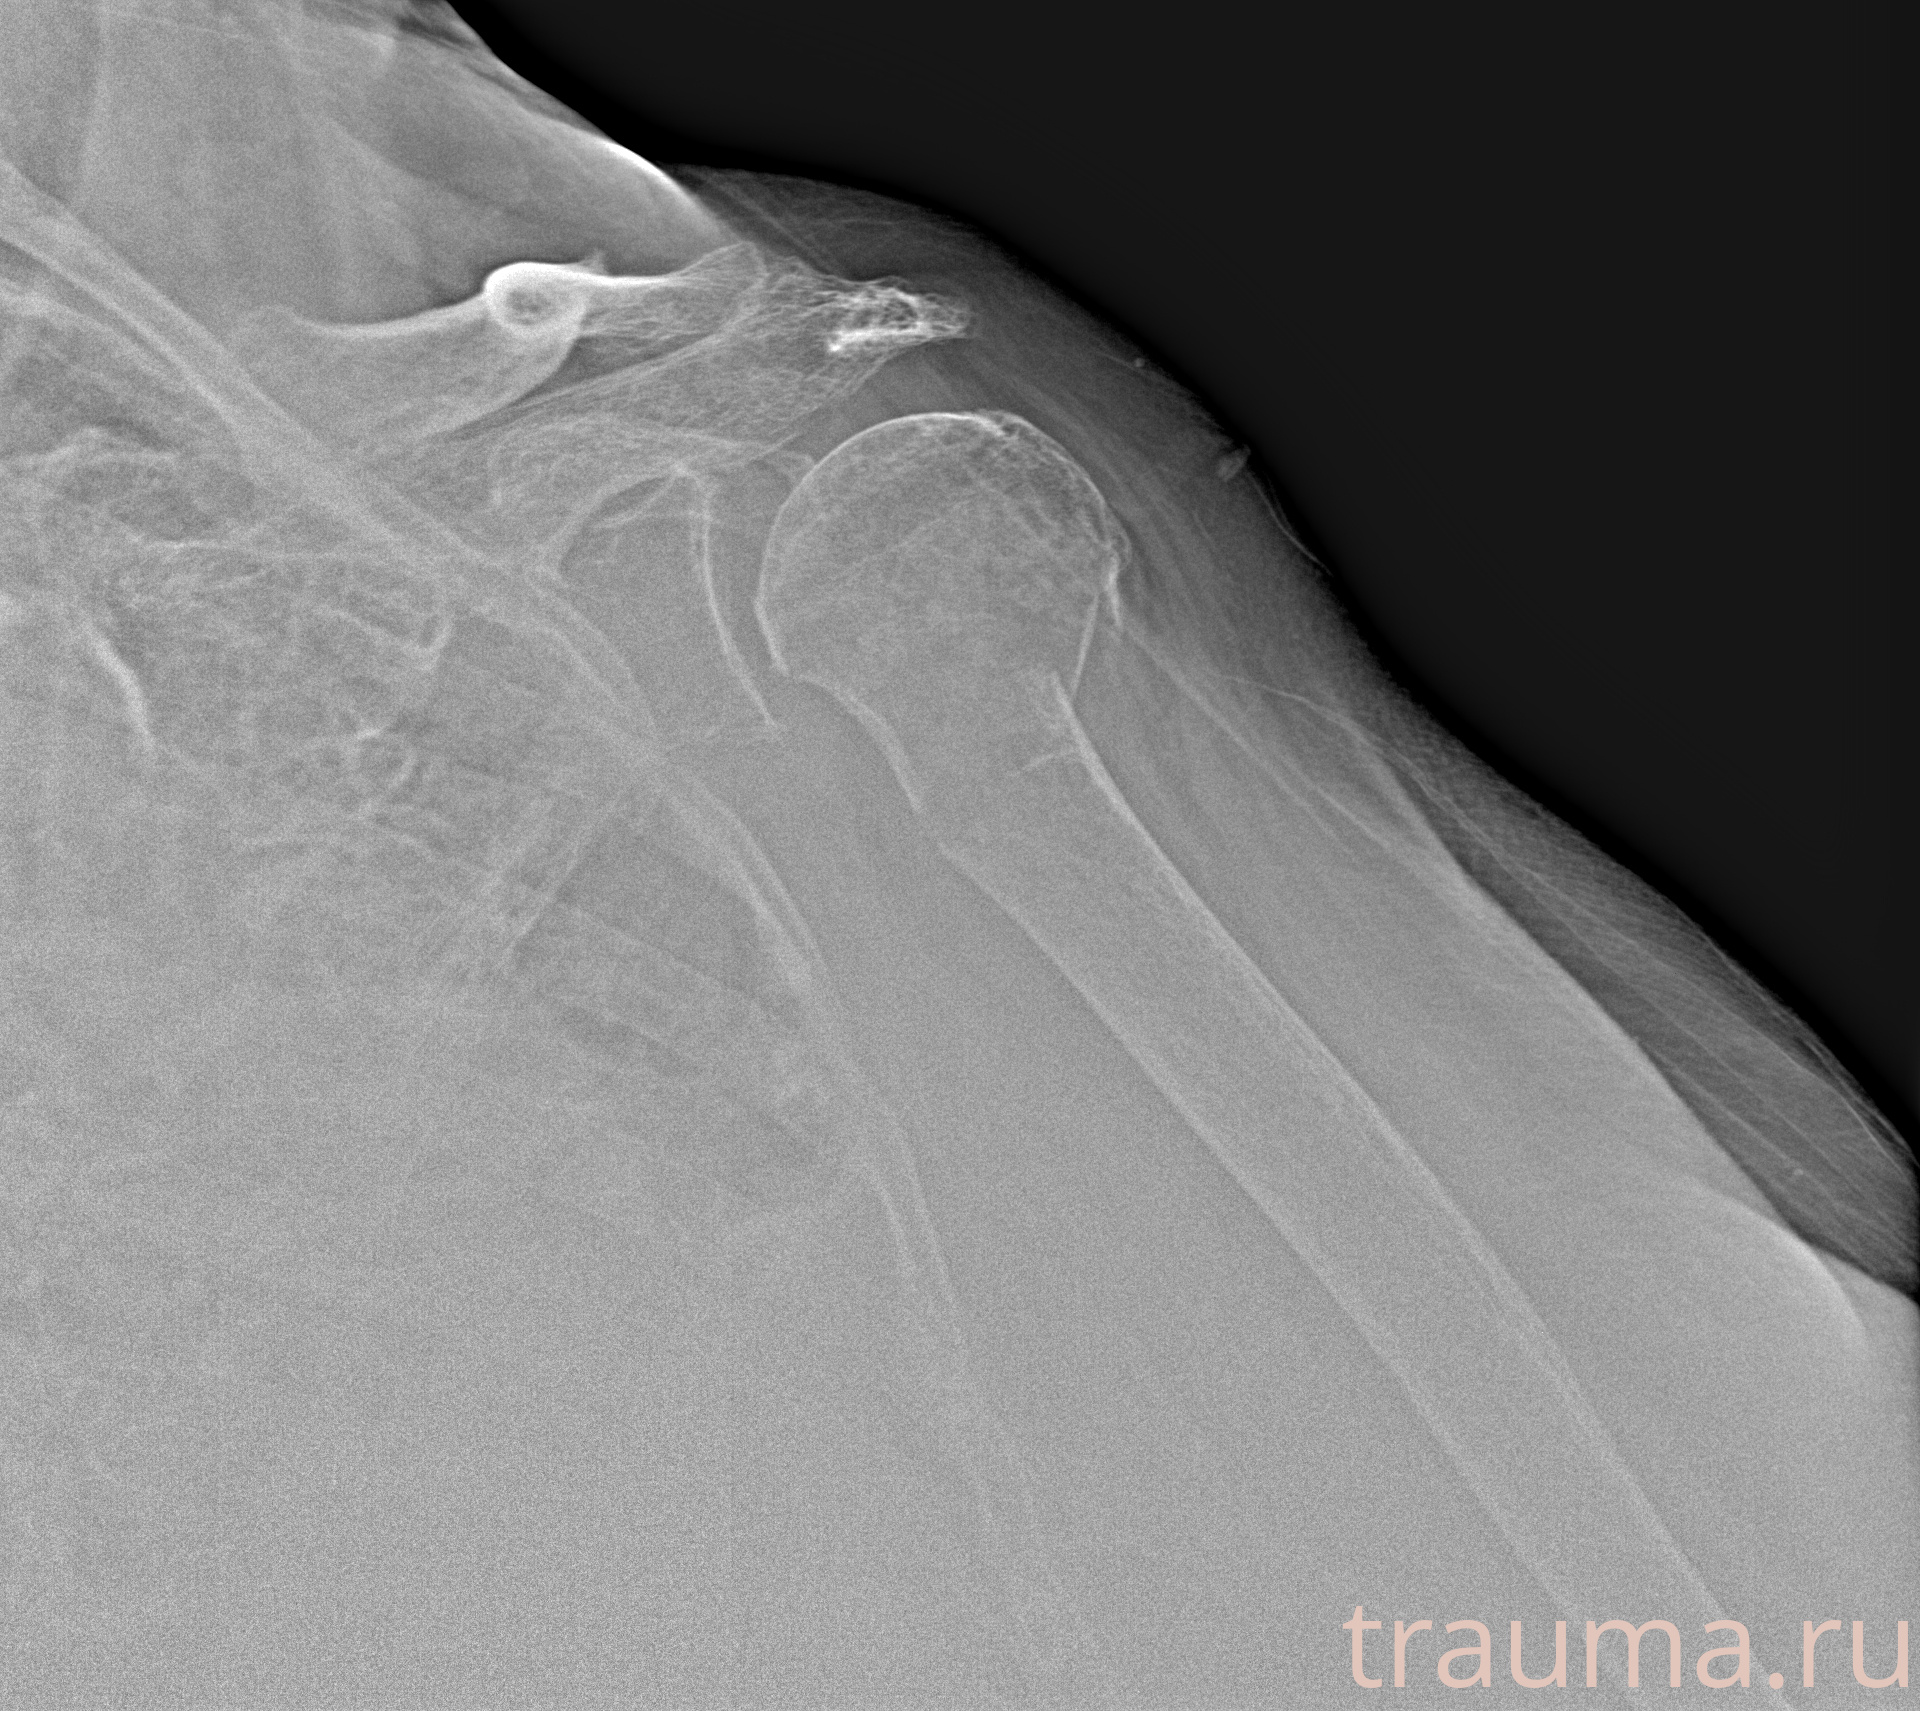

Рентгенограммы

Рентген на дому: по вашему адресу приезжает врач-рентгенолог, травматолог-ортопед с мобильным рентгеновским аппаратом, проводит диагностику травмы или заболевания, делает необходимые рентгенограммы, дает рекомендации по дальнейшему лечению. Получить качественные снимки в домашних условиях возможно благодаря уникальной методике, разработанной МосРентген Центром для института  Склифосовского